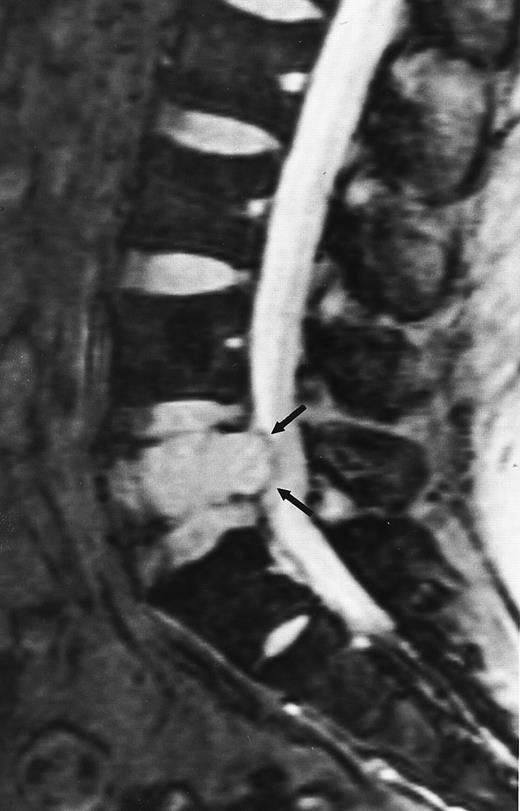

A 38-year-old man with solitary plasmacytoma of L5. Relatively T2-weighted gradient recalled echo (400/21, TR/TE, flip angle 20°) sagittal MR image of the lumbar spine shows bright signal of mass in L5 and extension of tumor into the spinal canal (arrows) with impingement of the thecal sac.